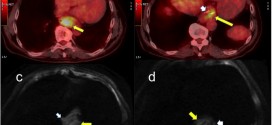

El esófago es un tubo muscular, hueco, que se extiende desde la faringe hasta el estómago, y sirve para el paso de alimento. En su recorrido, atravesando el cuello y el tórax para llegar al abdomen, se encuentra por delante de la columna vertebral, en íntima relación con distintas estructuras (aorta, nervio recurrente laríngeo izquierdo, bronquio principal izquierdo, corazón y …

El cáncer de esófago. Tumor maligno en general y especialmente formado por células epiteliales. El esófago es el tubo hueco, muscular que transporta los alimentos y los líquidos desde la garganta al estómago. La pared del esófago comprende varias capas de tejido, incluyendo la membrana mucosa, músculo y tejido conjuntivo. El cáncer de esófago comienza en el revestimiento interior del …